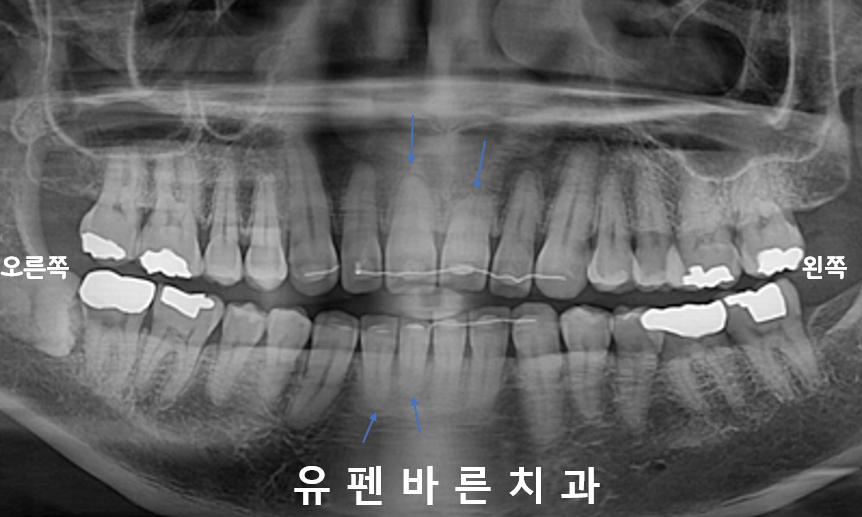

엑스레이를 확인해보니

치아의 뿌리들이

흡수되어

짧아져있었습니다,,